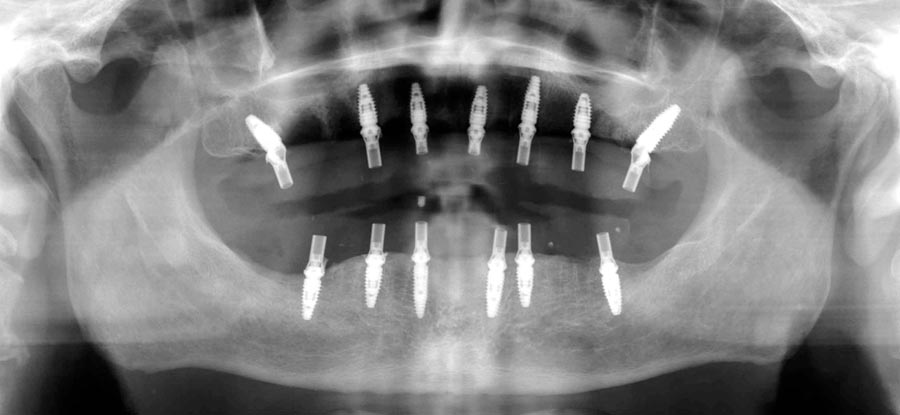

Smile GalleryImplant RestorationsFull Mouth Implant Restoration 1 of 13 Pre-operative smile Pre-operative smile Pre-operative frontal view, lips retracted Pre-operative panoramic image (note bone levels) Post-surgical panoramic image Surgical temporary bridge (note convex contours) Delivery of surgical temporary bridges in both upper and lower Two weeks post-op surgery and temporaries (note amazing tissue response) Three months post- surgery. (Note tissue development) Definitive implant bridges (FP-2) Post-treatment panoramic image Final result smile Final result smile